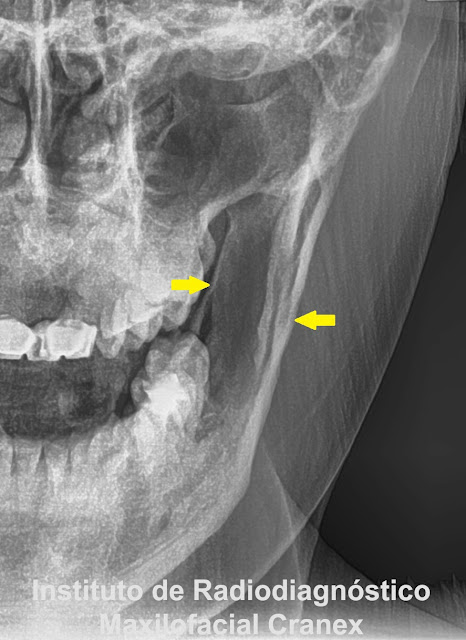

| Fig. 1. Radiografía panorámica. |

| Fig. 2. Radiografía Panorámica (Close up - piezas 4.5, 4.6) |

A la evaluación de la radiografía panorámica observamos: Una imagen radiolúcida unilocular en el cuerpo

mandibular derecho, de límites definidos y bordes corticalizados finos, proyectada

sobre tercio medio y apical de piezas 4.5 y 4.6; con aspecto festoneado en

sentido cefálico. Signos radiográficos compatibles con “Quiste óseo Simple”.

Radiográficamente el

QOS, Se presenta como una imagen radiolúcida

unilocular o multilocular bien definida o irregular, de bordes corticalizados

finos, usualmente presenta un aspecto

festoneado a nivel de las raíces dentarias, el 14.83% de los casos puede

presentar borramiento o ausencia de la lámina dura; en zona de molares se

observa por encima del canal mandibular y algunos estudios reportan lesiones

bilaterales o en el cóndilo mandibular.8.